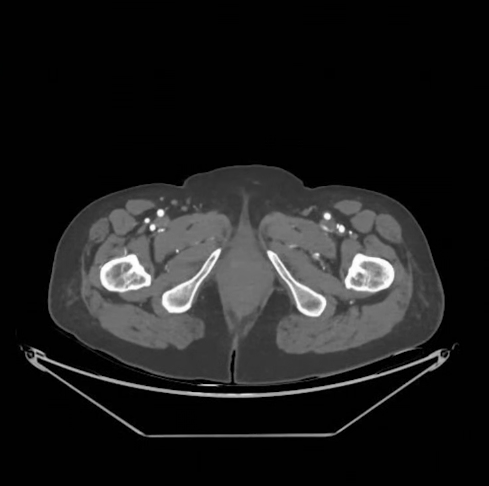

术前检查

ABI:右侧为0.51;左侧因膝下血管闭塞,ABI未测出。

CTA:左侧股浅动脉中上段存在长段狭窄及闭塞病变,病变长度约15cm;膝下三支动脉主干闭塞;足远端经侧支循环显影,且显影速度缓慢。

CTA